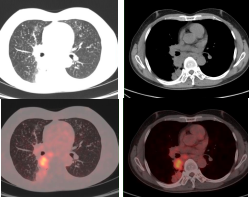

肺癌放疗前确定生物靶区:左肺下叶鳞癌患者(右图所示),左下肺癌病灶并远端阻塞性肺不张,PET/CT可以准确区分肿瘤组织与非肿瘤组织,确定肿瘤病灶生物靶区。

早期肺癌发现及鉴别:PET/CT显像示左肺上叶前段软组织灶(左图所示),糖代谢明显增高(SUVmax=15.3),经手术病理证实为肺腺癌。